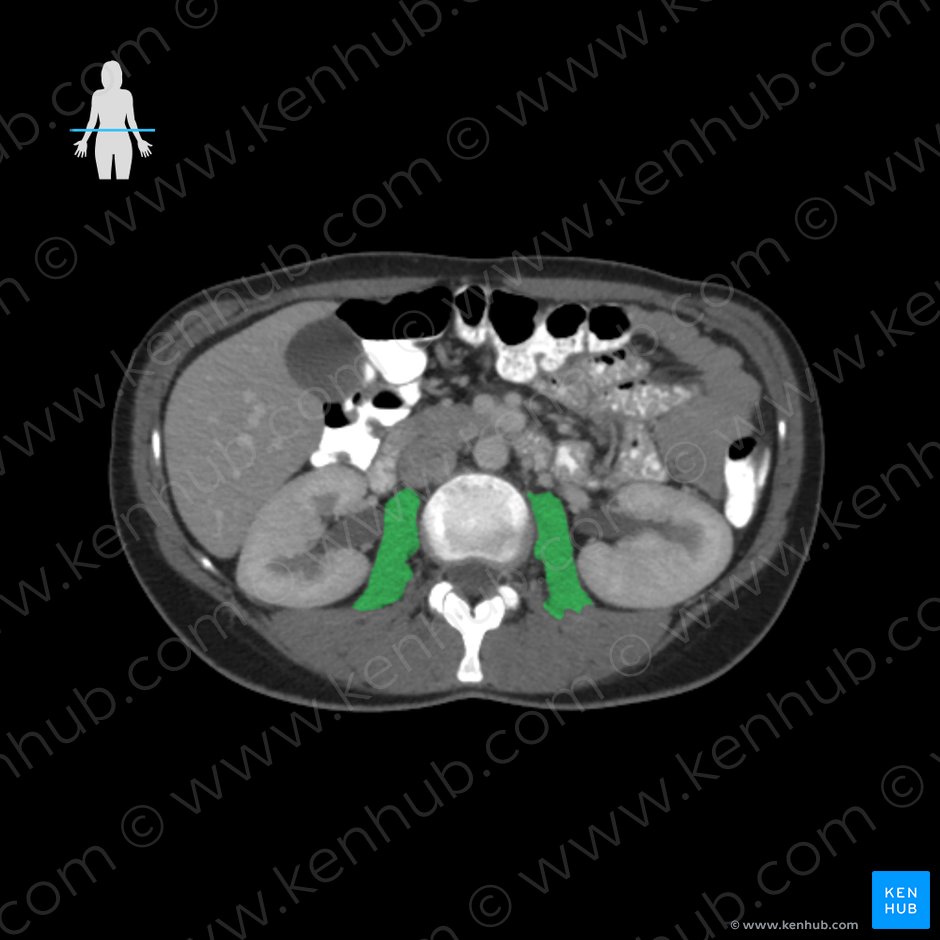

대요근 : 초록색, 장요근: 분홍색 (1) 대요근(psoas major)

origin: 전방부- L1-L5 척추체와 디스크의 옆면

후방부- T12-L4까지 횡돌기의 전면

(Vertebral bodies of T12-L4,

intervertebral discs between T12-L4,

transverse processes of L1-L5 vertebrae)

장요근은 척추체에서 시작되는 대요근과

골반 안쪽에서 시작하는 장골근 두 근육이

하나로 합쳐져 대퇴골 소전자에 부착하는 근육입니다.

척추와 골반의 안정화 및 요통 치료에 아주 중요한 근육입니다.